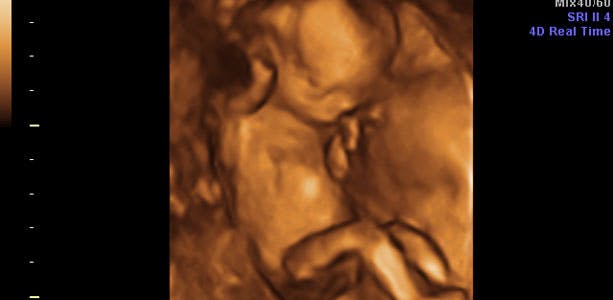

Gravid uge 16: Hår, øjenbryn og negle

Nu har baby fået hår, øjenbryn og tydelige negle. Nogle gange får det også hikke af at drikke fostervand - det mærker du senere i graviditeten, når barnet er blevet lidt større. I slutningen af ugen, måler barnet omkring 16 centimeter i fuld længde og vejer cirka 200 gram. Hovedet måler cirka 3,5 centimeter mellem ørerne (BPD, som også kaldes bipariatal diameter, og som er målet fra øre til øre).